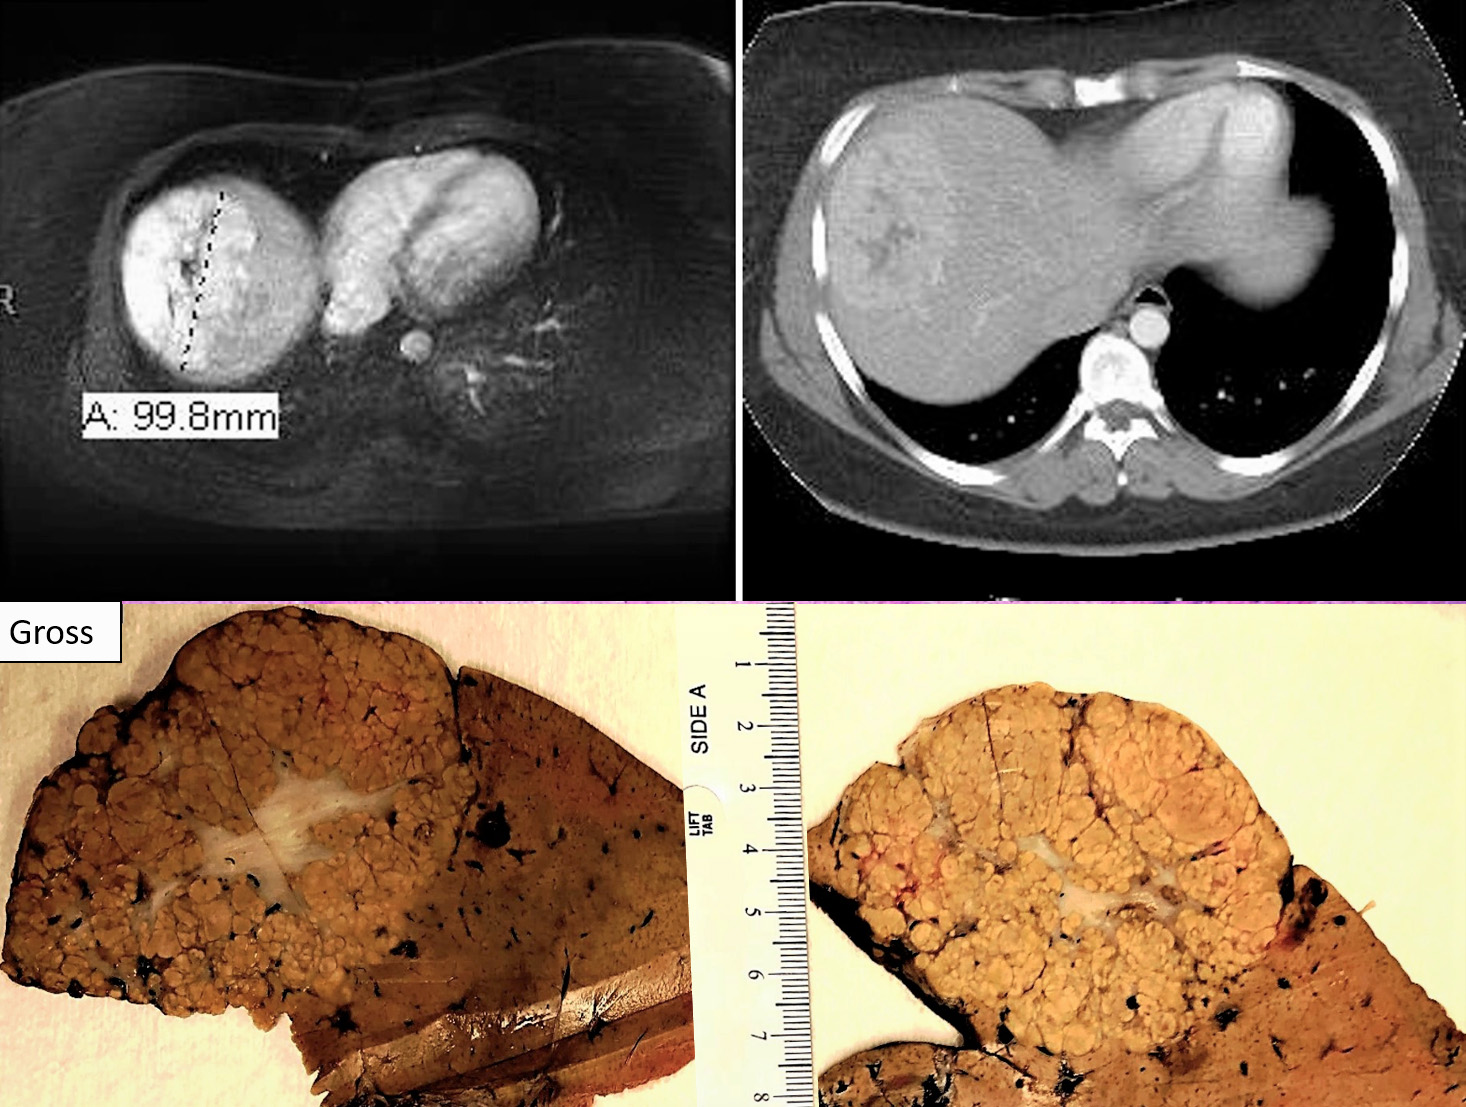

A 24 year old African American female with right upper quadrant abdominal pain & amenorrhea (2nd to Depo-Provera use for approximately 9 yrs.). CT scan showed poorly defined lesion at hepatic dome with irregular central hypoattenuation.

Focal nodular hyperplasia (FNH) is reactive lesion that is composed of hepatocytes and bands of fibrosis that occur due to vascular shunting in noncirrhotic liver. Usually FNH is a single lesion that most often seen in young and middle-aged women. Macroscopically, it is well-demarcated tan sub capsular mass with central stellate scar. Histologically, on low magnifications, it resembles cirrhosis with nodularity and band of fibrosis. The hepatocytes lack cytologic atypia. Multifocal areas of bile ductular proliferation (metaplasia) often seen at the interface of the hepatic parenchyma and the fibrous bands. Abnormal thick walled arteries are present in the center of the fibrous bands. Glutamine synthetase immunohistochemical stain shows an irregular blotchy/patchy pattern “maplikepattern”. While it has diffuse staining pattern in both hepatic adenomas (Beta catenin mutated) and HCC. The lesional cell show shows low proliferation index by Ki 67 immunohistochemical stain (<1%). Glypican-3 immunostain is negative. Reticulin special stain demonstrates normal reticulin pattern. It was hypothesized that FNH might be a precursor to FLC. However, there has been no proof until now to support this idea. The FNH that surrounds a small subset of FLC considers as a reaction to the tumor itself and not a precursor. [6]

Fibrolamellar carcinomas (FLCs) arise in noncirrhotic livers of older children and young adults. They compromise about 1%-9% of all HCCs according to the SEER (Surveillance, Epidemiology and End Result program) database. [1] Edmondson described FLC in 1956 [2] then term FLC was suggested in1980 by Craig et al; [3] However; it took until 2010 for the World Health Organization (WHO) to designate this clinical entity with its own WHO classification number. [4] They usually present with nonspecific signs and symptoms along with normal serum AFB levels, but in ~ 5-10%, the AFB level could reach up to 200 ng/mL. FLCs have an overall better prognosis than other primary liver tumors (e.g., HCC, intrahepatic cholangiocarcinoma). [5] The most important prognostic feature is whether the tumor is resectable or not. [6,7]